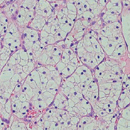

Wat doet een patholoog?

Magazine over blaas- en nierkanker | nr. 62 maart 2018 | Tekst: Jolanda Thelosen "De patholoog richt zich van oudsher op het…